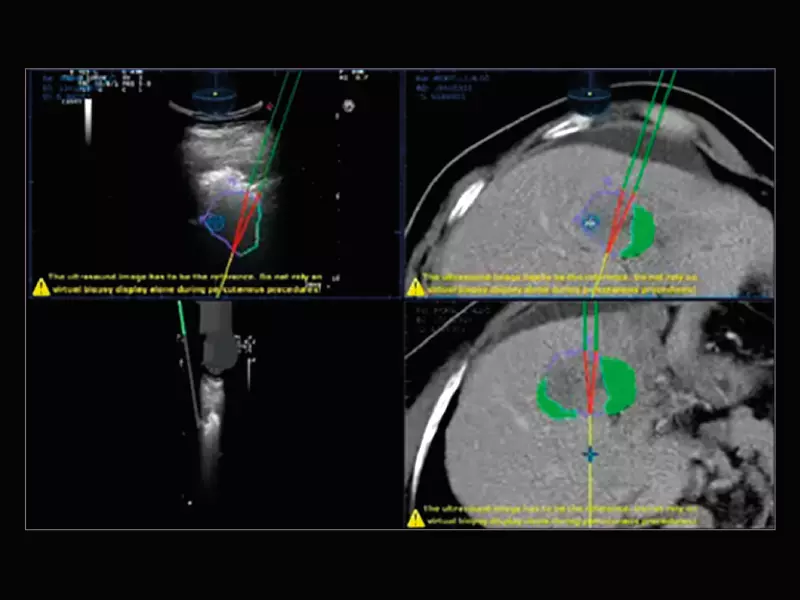

MyLab™9 Platform - Precise lesion detection and guidance with Virtual Biopsy

MyLab™9 Platform - Precise lesion detection and guidance with Virtual Biopsy